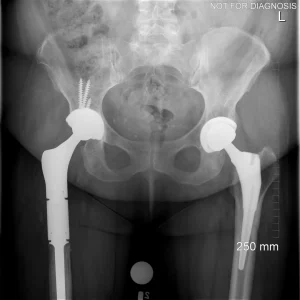

Hip resurfacing is a type of hip surgery used to treat hip arthritis, most commonly in younger and more active patients. Unlike a total hip replacement, hip resurfacing preserves more of your natural thigh bone. Instead of removing the entire femoral head (ball at the top of the thigh bone), the damaged surface is trimmed and covered with a smooth metal cap. The hip’s socket on the pelvis is also fitted with a metal cup.

- Preserves more natural bone compared to total hip replacement

- Easier conversion to total hip replacement if needed in the future

Hip Resurfacing vs. Total Hip Replacement (THA)

Hip Resurfacing

- Preserves more natural bone (the femoral head is capped rather than replaced)

- If needed, it can usually be revised to a total hip replacement

Total Hip Replacement (THA)

- Removes the femoral head and replaces it with a stem and ball

- Replaces the socket with a cup and liner (many bearing options exist)